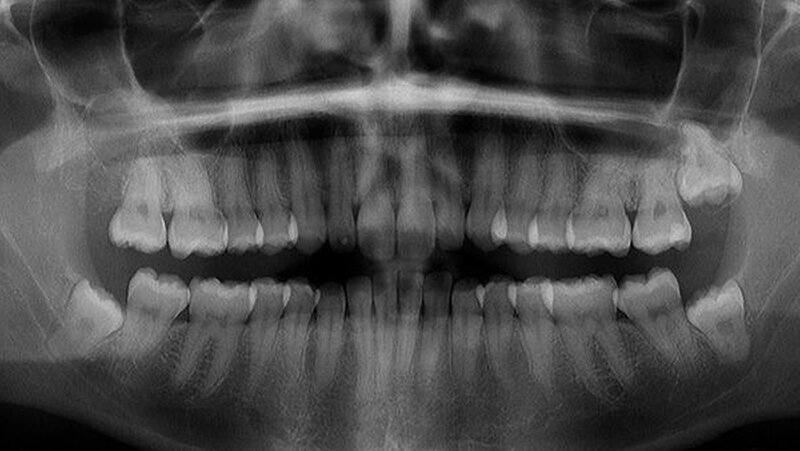

In der regionalen Klinik (Winterberg-Krankenhaus Saarbrücken) wurde zusätzlich eine kontrastmittelunterstützte Computertomografie der Nasennebenhöhlen durchgeführt (Abbildungen 2 und 3), die den Befund bestätigte und präzisierte.